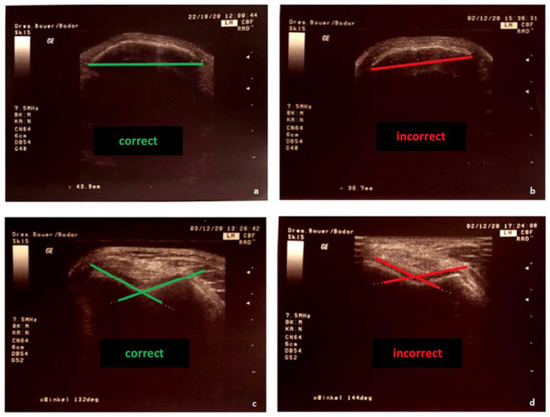

Therefore, the transducer was placed in a suprapatellar transverse plane using the extension of the femoral axis. The ultrasonic images were adjusted as necessary to obtain the maximum angle and echogenic cartilage, possible and a continuous strong echo line marking the bone (Figure 2). Correct and incorrect plane adjustments are also shown in Figure 2. A measuring protocol was developed for the standardization of the measurements. Examiner 1 started the measurement series by measuring the transverse patellar diameter, followed by Examiner 2. For blinding, values were hidden on the screen. The final adjusted image with the measurement result was printed. Then Examiner 1 positioned the tested knee in 100° flexion and measured the sulcus angle, followed by Examiner 2, also with covered values. The second measurement session took place after approximately 45 min, as analog to the first. Consistently in this study, the right knee joint was measured

Figure 2. Image settings for sonographic measurement: (a) correct measurement of the patella diameter, (b) incorrect measurement plane, (c) correct positioning of the lines for the angle measurement, (d) incorrect positioning of the lines.